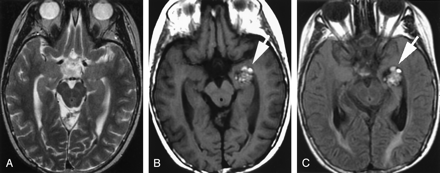

A, Axial T2-weighted MR image obtained 12 years after craniospinal radiation therapy at 3 years of age for a posterior fossa medulloblastoma showing no lesion in the left temporal lobe/temporal horn.

B, Axial T1-weighted and, C, fluid-attenuated inversion recovery (FLAIR) MR images obtained 15 years after the radiation therapy, showing a lobulated area of mixed signal intensity with peripheral hypointense rim (white arrow) in left medial temporal lobe/temporal horn, typical “popcorn” MR appearance of a cavernous angioma.